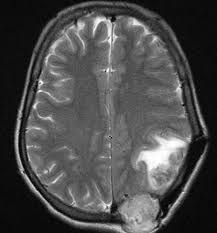

Thyroid Cancer Archives Oncoplus Hospital from www.oncoplus.co.in Find out more about thyroid cancer's symptoms, signs, causes, diagnosis, treatment, survival rate, and risk factors. If you notice a new or growing lump, you should see your doctor, who can run additional tests to identify the cause and determine if it is a tumor. Most of the symptoms of thyroid cancer, if it is large enough, tend to be from compression of anatomical objects located in the neck (4). Metastases to the thyroid are an uncommon cause of thyroid malignancy. Symptoms of anaplastic thyroid cancer include a rapidly growing neck lump that is large and firm, as well as hoarseness, problems swallowing lung metastasis may cause a variety of symptoms like trouble breathing, shortness of breath, chest pain, or cough, whereas bone metastasis may cause. What are the symptoms of thyroid cancer? Thyroid cancer that recurs can be treated. Both occur particularly with liver metastasis, and either symptom may be the first manifestation of the disease.

Signs of an overactive or underactive thyroid generally develop slowly, anywhere between a handful of weeks to signs and symptoms of all thyroid problems are fairly similar to a variety of other medical conditions. During his conversation with tert.am, slavmed medical center's endocrinologist vahe avagyan described the main types of thyroid disease in detail, its symptoms, and when one. If cancer is diagnosed, relieving symptoms remains an important part of cancer care and treatment. The uzi signs of thyroid cancer are conducted in order to detect this disease. Examination in patients suspected of thyroid cancer includes the following however, the rate of distant metastasis is significantly increased (approximately 20%). Spread of the cancer from the initial organ where it developed to other organs, such as the lungs and bone. Learn more about thyroid cancer and its types, as well as signs and symptoms, diagnosis, staging and thyroid cancer treatment information. The number of people suffering from thyroid disease is constantly increasing all over the world, including armenia. Occasionally a patient will have flushing episodes. Sometimes, people with thyroid cancer do not have any of these changes. Thyroid cancer is not considered the most common form; The abnormal cells begin multiplying in your thyroid and, once there are enough of them, they it's rare, and it is the hardest to treat. Thyroid cancer develops in the thyroid gland, a part of the endocrine system.